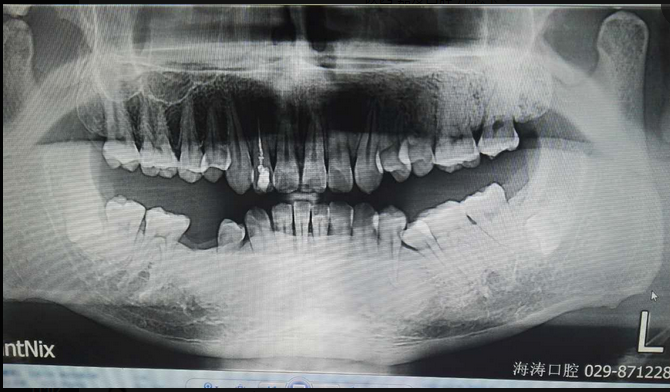

倒置阻生牙拔牙的病案討論

討論四:片子顯示的倒置阻生牙撥牙關(guān)健注意幾點(diǎn),1.翻瓣后去骨部位盡量離7遠(yuǎn)中,別破壞7遠(yuǎn)中骨壁,避免損傷7,以去除8根部的阻力為主。2.暴露阻生牙后,用鉆磨斷部分冠根后,用小骨鑿劈裂冠與根,可避免牙鉆因視野而誤傷神經(jīng)。3.冠根裂開(kāi)后,先用牙挺挺出根部,然后挺出冠部。

提問(wèn):對(duì)7號(hào)牙沒(méi)有影響的埋伏智齒,是不是可以不拔?

答:一般情況下,完全骨埋伏阻生牙患者如無(wú)不適癥狀不會(huì)要求撥牙的,很多時(shí)候是口腔內(nèi)其它問(wèn)題拍片時(shí)發(fā)現(xiàn),但醫(yī)生發(fā)現(xiàn)這種情況要告知患者將來(lái)可能會(huì)發(fā)生什么問(wèn)題,例如頜骨囊腫,7號(hào)牙松動(dòng)等等,畢竟這個(gè)8號(hào)牙是潛在的病灶牙,究竟撥與不撥得讓患者作主,我們得盡到告知義務(wù)。往往最后決定撥這類(lèi)牙的患者都是有各種不適癥狀的。

至于對(duì)7號(hào)牙暫時(shí)沒(méi)有影響的埋伏牙,不等于以后永遠(yuǎn)不影響。